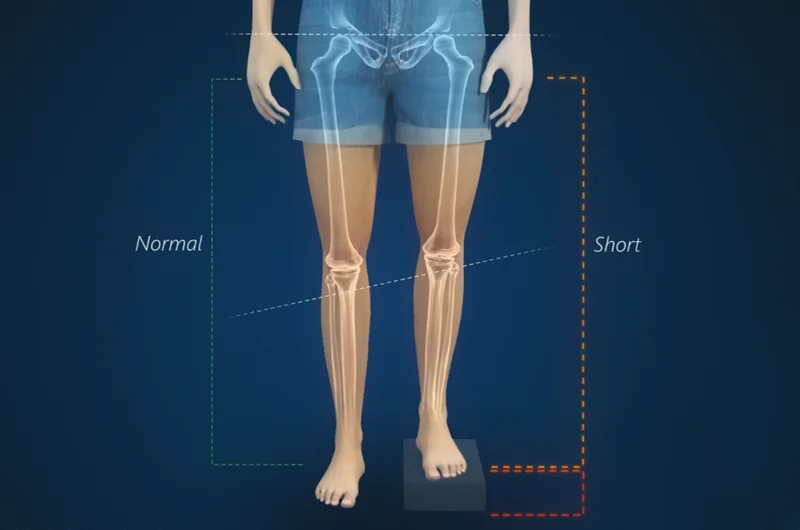

Deformidades Articulares

Algumas deformidades articulares, sejam elas congênitas ou adquiridas, podem causar dor e limitação de movimento. Em certas situações, a reconstrução óssea e articular pode ser indicada para corrigir essas deformidades e melhorar a função da articulação.